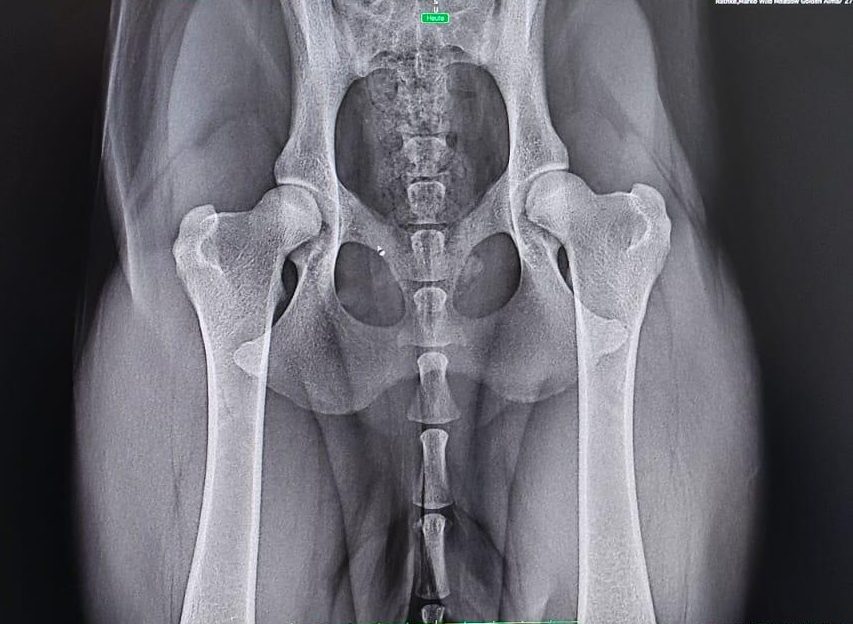

Das HD-ED Röntgen steht an . . .

Freitag, 18.07.2025 und Freitag, 22.08.2025

... mit neun Hunden

in Kleve bei DR. H. Camp

Zum ersten Termin kommen fünf Hunde unseres A-Wurfes: Peanut (Rüde Rot), Frieda (Hündin Hellgrün), Mika (Hündin Orange), Lilly (Hündin Lila) und Amber (Hündin Schwarz). Zum zweiten Termin kommen noch Alva (Hündin Blau), Ella (Hündin Rot), Ellie (Hündin Dunkelgrün) und Lua (Hündin Gelb). Anton (Rüde Blau) ist – da er jagdlich ausgebildet wird – zum DRC gewechselt und wird bei seiner TÄ geröngt.

Alle lassen die Prozedur des Narkotisieren, Röntgen, Beurteilen und wieder Aufwachen brav über sich ergehen und wir werden mit tollen Ergebnissen belohnt: 7 x A1/A1 und ED frei und 3 x A2/A2 und ED frei.